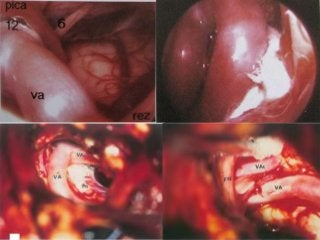

A nontoothed forceps is used to hold the soft tissues (ST) surrounding

the nerve at the level of the stylomastoid foramen (SMF), and

sharp scissors are used to dissect the soft tissues from the bone at that

level. C Cochlea, FN(m) Mastoid segment of the facial nerve, LSC Lateral

semicircular canal, NC New canal, SS Sigmoid sinus

Rerouting of the facial nerve. FN(m) Mastoid

segment of the

facial nerve, FN(p) Intraparotid facial nerve, SM

Facial nerve at the stylomastoid

level, ST Soft tissues

The facial nerve has been rerouted into the new

canal (*).

FC Fallopian canal, FN(p) Rerouted part of the

intratemporal facial nerve,

FN(t) Rerouted part of the tympanic segment of

the facial nerve, ST Soft

tissues